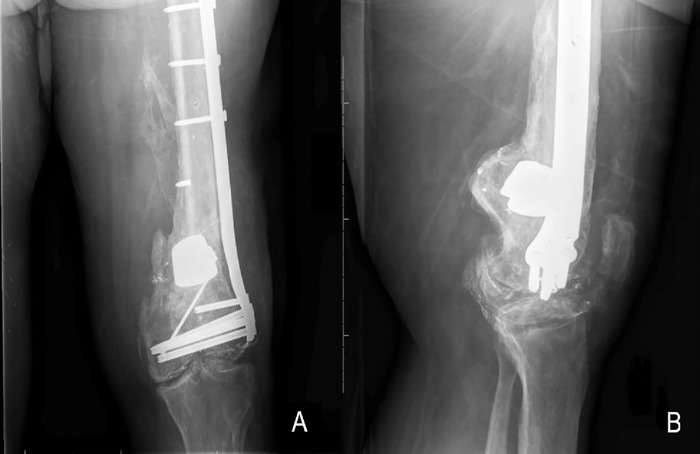

Case report: A 54-year-old male was involved in a high-speed motor vehicle accident that resulted in a left distal femur fracture. The patient underwent multiple reconstructive procedures that were complicated by hardware failure and recurrent nonunion. Prior to the sixth reconstruction, a superficial femoral artery occlusion was discovered and addressed with endarterectomy. The sixth and final procedure resulted in osseous union and stable fixation of the femur fracture.

Conclusion: A missed superficial femoral artery occlusion likely contributed to the delay in achieving osseous union of a traumatic comminuted distal femur fracture.